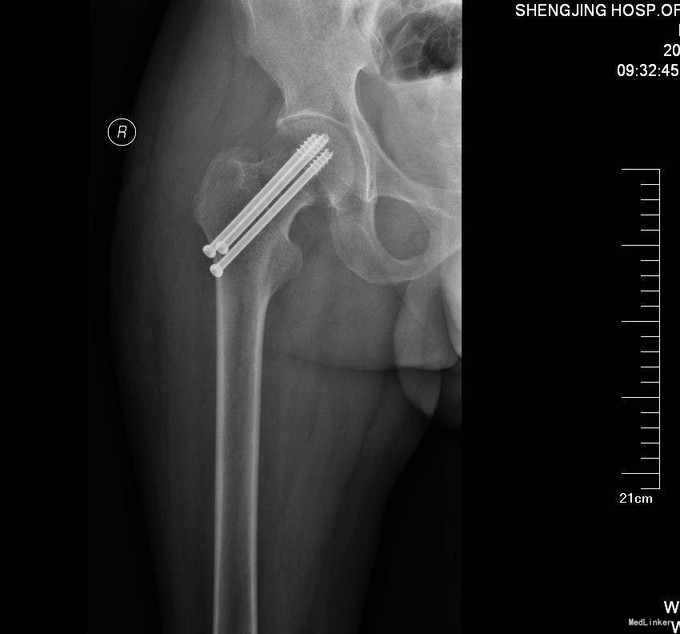

患者入院后完善相关检查,患者未满65周岁,所以择期行右股骨颈骨折闭合复位空心钉内固定术,术后患者3天后出院。